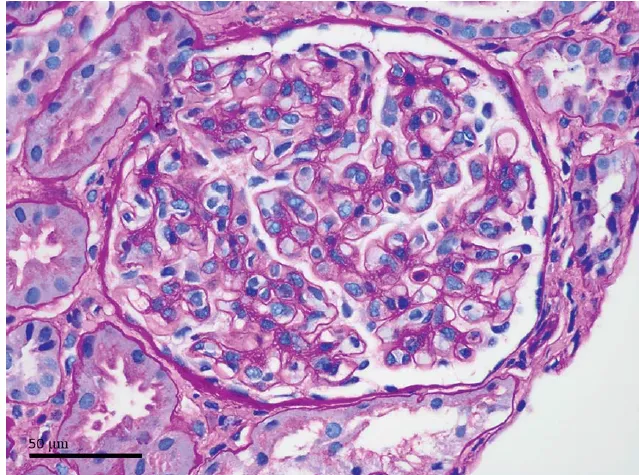

Paciente com antecedentes de carcinoma de células renais claras ressecado previamente, apresenta em exame de controle a seguintes imagens.

Na imagem 1: Um pequeno tumor exofítico com realce se projetando a partir da face anterior do polo superior do rim esquerdo (seta). Além disso, há uma lesão de 4 mm na face posterior do rim direito. Paciente foi submetido à enucleação cirúrgica da lesão renal esquerda. O tumor renal direito foi tratado com ablação por radiofrequência.

Nos pacientes múltiplos tumores renais devemos suspeitar imediatamente de Doença de Von-Hippel Lindau, nesses casos devemos procurar tratamentos que visem poupar massa renal, uma vez que a recorrência dos tumores é a regra.